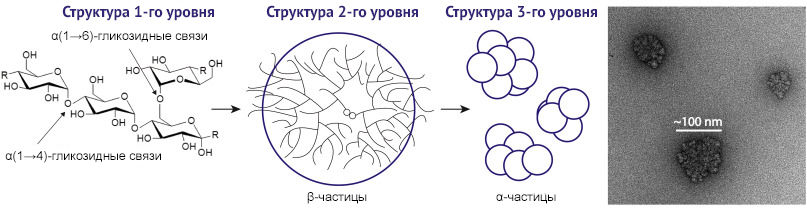

Значение гликогена в повреждении почечной паренхимы при сахарном диабете определяется его конформационными превращениями (рис. 2) [2]. Наличие большого количества ветвлений и небольшая длина цепочек (12–18 глюкозных остатков) в молекуле обеспечивает быстрое высвобождение концевых мономеров при распаде гликогена.

Образование более длинных цепочек глюкозы в гликогене снижает скорость его деградации, а наличие сверхдлинных цепей и вовсе приводит к его патологическому накоплению в клетках. Длинные цепи образуют нерастворимые двойные спирали, которые со временем осаждаются и теряют способность отщеплять накопленную глюкозу. Такие полимеры глюкозы называются полиглюкозанами и обнаруживаются при различных гликогенопатиях. Например, миоклонус-эпилепсия Лафоры, при которой мутации в генах лафорина и малина, участвующих в обмене гликогена, приводят к накоплению его в виде нерастворимого полиглюкозана — телец Лафоры. Болезнь Андерсена (амилопектиноз, гликогеноз IV типа) характеризуется недостаточностью амило-1,4:1,6-глюкантрансферазы (гликоген-ветвящего фермента), что также приводит к избыточному накоплению в различных тканях (печени, селезенке, лимфоузлах, в меньшей степени — в миокарде, слизистой оболочке кишечника) аномального полисахарида с амилопектиноподобной структурой, что повреждает клетки. Аналогичные перестройки молекулы гликогена рассматриваются как возможный механизм поражений Армани-Эбштейна крайней степени [5].